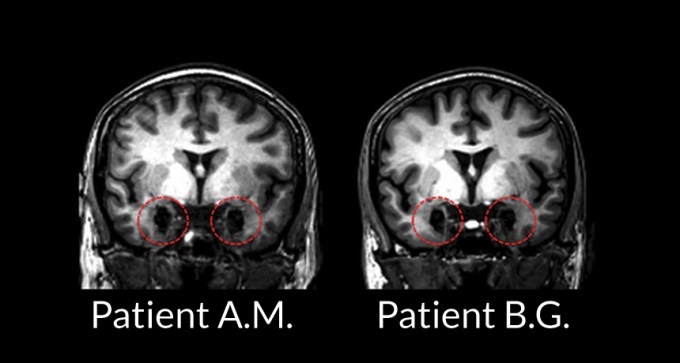

2. Neuroscience

Brain holds more than one road to fear

A study on rare patients suggests that fear can take many paths through the brain.